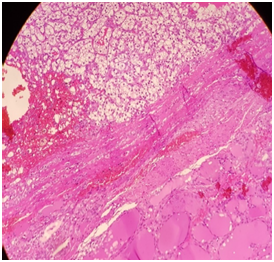

In May 2016, CT thorax abdomen and pelvis for assessment of weight loss revealed no evidence of renal cancer recurrence, but there was a heterogenous right thyroid lobe lesion measuring 2.3cmx1.8cm. Subsequent ultrasound assessment of this thyroid lesion showed a right lobe solid and isoechoic nodule with few cystic areas measuring 3.5x2.74cm. There were other small nodules less than 0.5cm in the left lobe. Fine needle aspiration (FNA) and cytology of the right lobe nodule in June 2016 was suboptimal, repeat FNA and cytology around 2weeks later was of borderline adequacy and the findings were non-specific. He proceeded for total thyroidectomy in July 2016, the histology revealed clear cell neoplasm with morphic features in keeping with metastatic renal cell carcinoma (Figure 1&2). Immuno- histochemical stain showed that the tumor was negative for thyroid transcription factor -1 (TTF-1) (Figure 3) and positive for CD10 (Figure 4). He was commenced on thyroid hormone replacement following thyroidectomy. Postoperative staging with positron emission tomography (PET) scan was unremarkable.6

Figure 1&2 Show the interface between normal thyroid tissue and the tumor.

Figure 3 The immunohistochemical stain, thyroid transcription factor-1 is positive for follicular adenoma and negative in metastatic renal cell carcinoma.